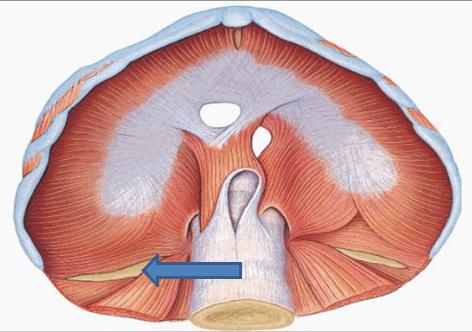

Анатомия диафрагмы и треугольника Бохдалека

Раздел: Визуальный дайджест